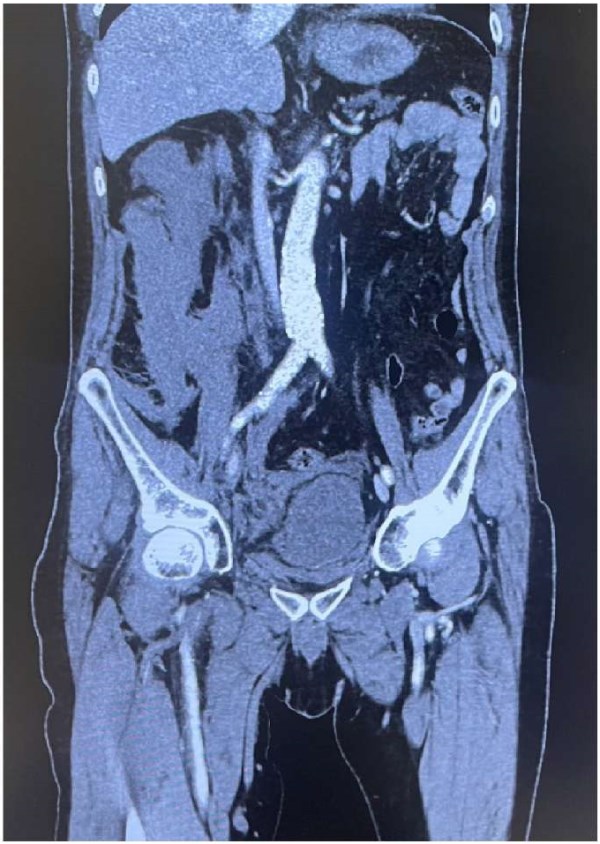

Профилактика осложнений определяется методикой доступа к бедренной вене, а также использованием вспомогательных средств визуализации сосудов. При использовании низкого доступа (>2 см ниже паховой связки) к бедренной вене могут быть повреждены ветви бедренной артерии (a. pudenda ext.), проходящие поверх бедренной вены, что может привести к серьезному интраоперационному кровотечению, образованию псевдоаневризмы и гематоме. С другой стороны, при применении высокого доступа (непосредственно под паховой связкой) повышаются риски забрюшинного кровотечения и гематомы (рис. 1). Применение ультразвукового контроля значимо понижает риски повреждения сосудов при проведении радиочастотной катетерной аблации (РЧА) ФП [7].

Рис. 1. КТ-картина крупной забрюшинной гематомы справа у пациента после радиочастотной изоляции ЛВ.